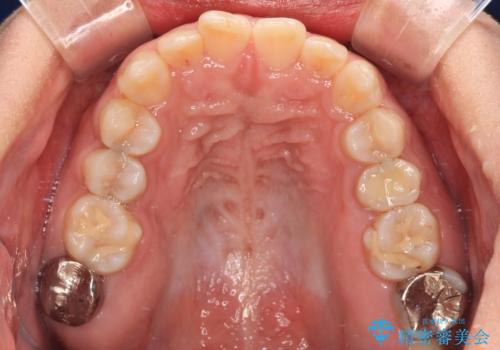

- 上下前歯の叢生を気にして来院された患者様です。

軽度な叢生であり、安価で短期間の治療を規模されていたため、インビザライン・モデレートを用いて矯正治療を行うこととしました。

インビザライン・モデレートは、製作できるアライナーの枚数に制限があるため、移動可能な量に限りがあるものの、インビザライン・ライトよりも枚数が多いため、幅広い症例に対応可能です。